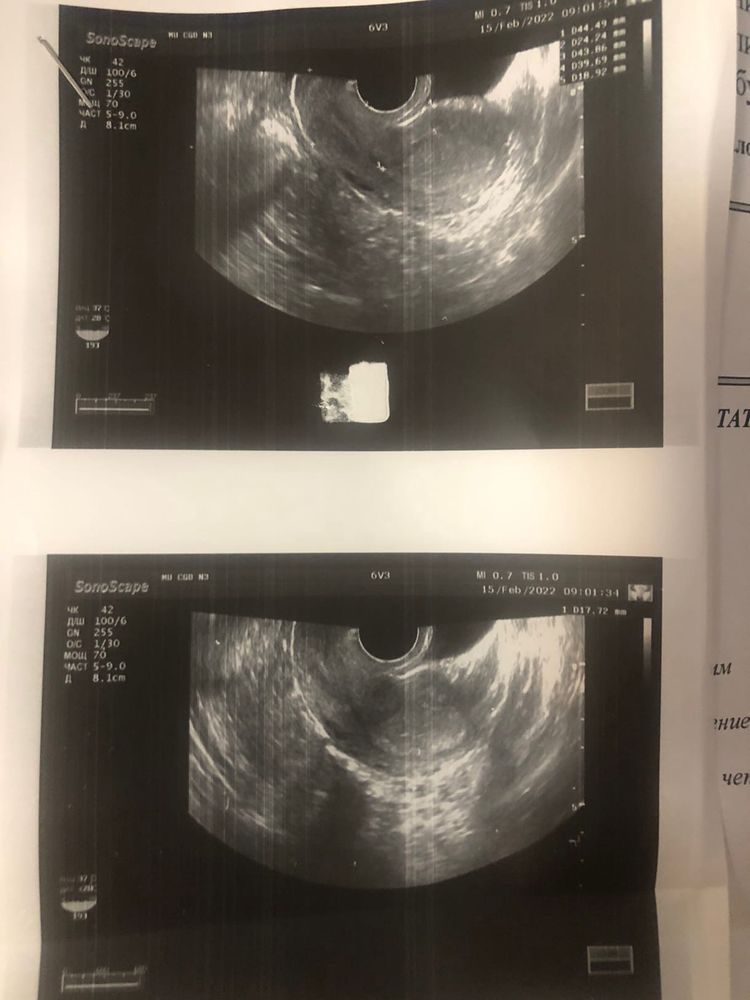

Слишком маленький срок и маленькое хгч, после 1000 могут увидеть и то не факт

При таком хгч ещё ничего и не видно на узи.

УЗИ после значения ХГЧ в 1000 Везде же это говорят

У меня плодное яйцо нашли при хгч выше 1295 При 1295 ничего не видели, через пару дней пошла в другую клинику - все увидели

Юлия Сергеевна, болел левый бок, мазало коричневым, но не постоянно. у меня долго не видели ничего, хгч дошел до 1000 только к 8 неделям, в 8,3 была операция. Бок болел уже прям очень сильно. Я сразу знала, что что-то не так. Это чувствуется

9 ДПО, ВСЕ РЕАГЕНТЫ В ИТОГЕ Яичник припаян к матке? На узи труб это бы увидели? И в заключении любого узи написали бы?